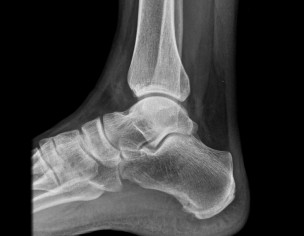

i am suffering PF pain for my both foot from last 3 years i took 4 times steroid injection & lot of pain killers tablets injections & some basic exercises but pain was same last November right foot Pf release surgery done in Multan Dr said left foot surgery after 6 months i came back here sharjah in January & from last week i am feeling pain left foot & as well right foot now after fresh X Ray & MRI here Dr diagnosed HEEL SPUR here Dr advised first physiotherapy i am going hospital daily for physiotherapy but still pain is same is there any permanent solution for this disease PF & HEEL SPUR kindly help me.